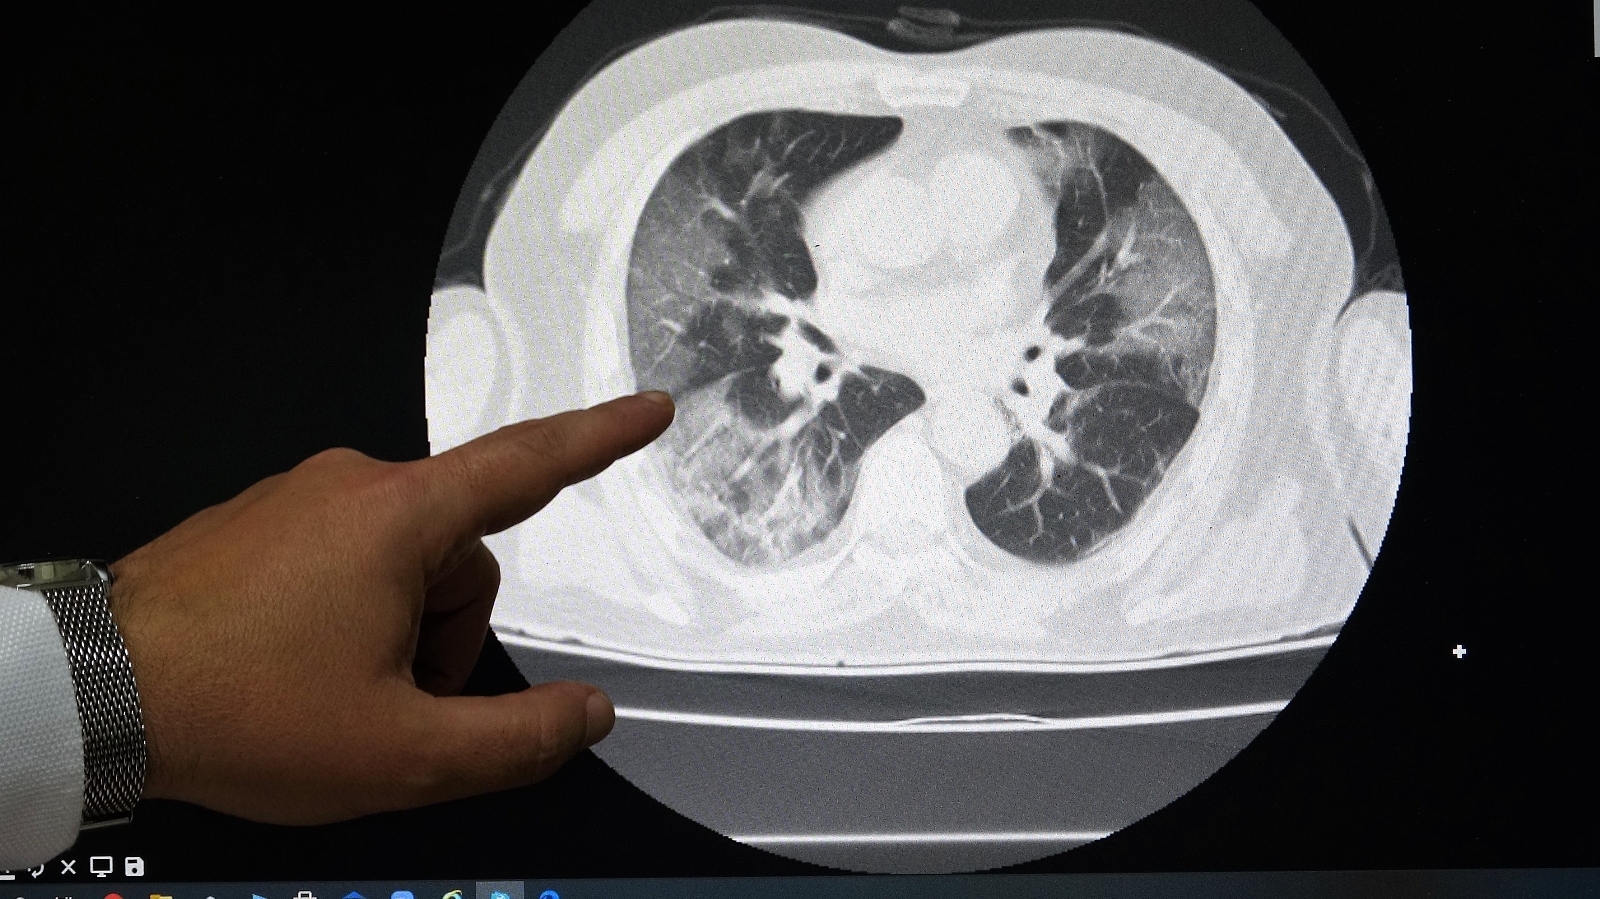

Aşısız Hastaların Akciğer Tomografisini Paylaşarak Uyardı

Hastanede yatan korona virüs hastalarının yüzde 90’nı aşısız